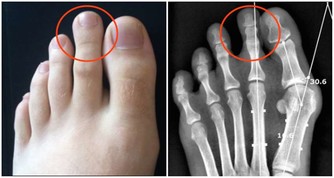

3、胸痛

常表現為胸部不規則的隱痛或鈍痛。大多數情況下,周圍型肺癌侵犯壁層胸膜或胸壁,可引起尖銳而斷續的胸膜性疼痛,若繼續發展,則演變為恆定的鑽痛。

持續尖銳劇烈、不易為藥物所控製的胸痛,則常提示已有廣泛的胸膜或胸壁侵犯。肩部或胸背部持續性疼痛提示肺葉內側近縱隔部位有腫瘤外侵可能。